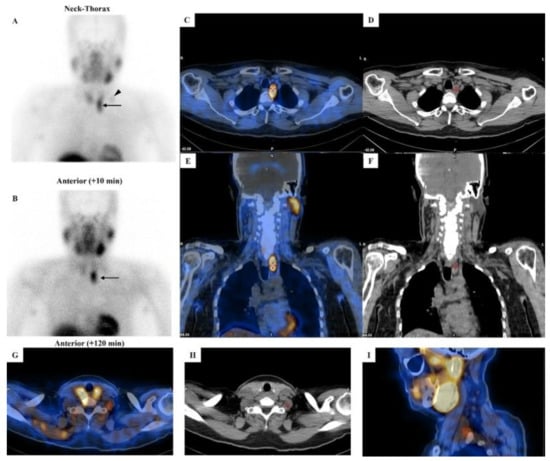

When combined with the US, [99mTc]Tc-MIBI scintigraphy achieves sensitivities of 81–95% for detecting hyperfunctioning parathyroid lesions [35,36,37]. Importantly, tracer retention patterns may suggest malignancy. Zhang et al. demonstrated that PCs exhibit significantly higher retention indices compared to benign parathyroid lesions, with distinct differences in both mean and peak retention values [38]. This finding highlights the potential of retention analysis as a non-invasive preoperative tool for differentiating malignant from benign parathyroid disease (Figure 3).

Figure 3. [99mTc]Tc-MIBI imaging in a patient with parathyroid carcinoma. Legend: A 52-year-old man affected by pHPT [intact PTH = 421.6 pg/mL (8–76), total calcium = 12.1 mg/dL (8.2–10.4), ionized calcium = 1.82 mmol/L (1.10–1.30)] due to PC. Neck ultrasound showed a hypoechoic and heterogeneous parathyroid lesion (28 mm in maximum size) close to the lower pole of the left thyroid lobe. Dual-phase parathyroid scintigraphy was performed using [99mTc]Tc-MIBI. Panels (A,B): Planar parathyroid images (anterior views) were obtained 10 and 120 min after [99mTc]Tc-MIBI administration (400 MBq). Early (panel (A)) and late (panel (B)) images showed a well-defined area of abnormal and intense tracer uptake located at the lower pole of the left thyroid lobe (black arrow). At visual assessment (i.e., qualitative analysis), the late image (panel (B)) showed a significant tracer retention in the parathyroid lesion. Using a semiquantitative approach, the peak Retention Index (RI) was suspicious for PC (peak RI = 11.45%). Panels (C,E): SPECT/CT imaging was acquired 130 min after [99mTc]Tc-MIBI administration. Axial (panel (C)) and coronal (panel (E)) images confirmed an abnormal tracer uptake located lower than the inferior pole of the left thyroid lobe (red cross-mark). At neck-thorax CT performed without contrast agent media administration (panels (D,F)), a large-sized (28 mm in maximum diameter) and non-homogeneous parathyroid lesion was noted just lower with respect to the inferior pole of the left thyroid lobe (red cross-mark). In addition, a faint but focal and abnormal tracer uptake was noted at the early planar image (panel (A)) in the middle-lower part of the left lateral neck (black arrowhead), consistent with lymph-node metastasis, which was then confirmed by hybrid imaging (red cross-mark in panels (GI)).

Semi-quantitative evaluation methods—such as delayed-to-early uptake ratio, tumor-to-background ratio on delayed images, and washout rate calculations—have been explored for preoperative differentiation [39]. However, retention indices can overlap between benign and malignant lesions, particularly in small tumors. Hence, further validation and methodological standardization are needed before these parameters can be integrated into routine clinical practice.